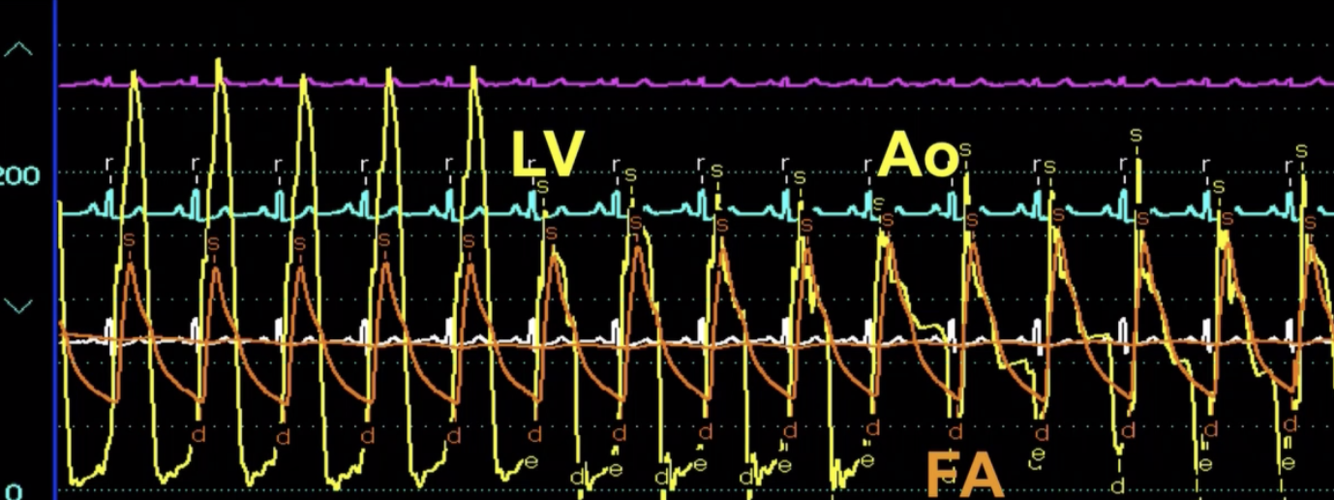

Describe the findings

HOCM: L heart pullback

Provocable Gradient: Valsalva Maneuver